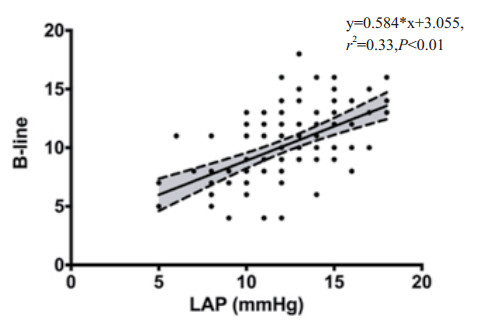

两组研究对象LUBS与LAP呈正相关,随着LAP升高,肺部B线逐渐增多,提示心功能越差,撤机的成功率越低, 见图 4。

| 图 4 两组LUBS与LAP(mmHg)的相关性 |

Pearson相关分析显示:LUBS与SBT 30 min BNP以及LAP均有显著性相关(分别为r=0.411,P < 0.01;r=0.628, P < 0.01)。BNP以及LAP数值增加,均可使LUBS增加。见表 2。

3 讨论撤机前对心功能、肺部评估及膈肌功能评估非常重要,由于床旁超声因其便携、实时、无创的优点,越来越多应用于机械通气患者的心肺功能评估。肺部超声B线评分可用于提供肺通气方面的量化比较[4]。Soummer等[8]证实肺脏超声可以通过识别整体或局部肺复张,对预测撤机失败具有一定的准确性。根据超声评估结果,可以让临床医生更好选择SBT的时机,进而对肺通气模式进行调整及优化[9]。本研究结果,LUBS与SBT 30 min BNP以及LAP均有显著性相关(分别为r=0.411,P < 0.01;r=0.628, P < 0.01)。BNP以及LAP数值增加,均可使LUBS增加,验证了LUBS也可以反应心功能情况。撤机成功组较失败组有着更低的B线积分(9.18±2.7 vs 13.2±2.1),提示失败组有更为严重的肺泡间质综合征,包括更差的心功能或肺部炎性渗出;LUBS的截断值> 9分,敏感性100%,特异性57.9%,AUC=0.862,阳性预测值34.1%,阴性预测值100%;提示在LUBS < 9分的情况下,撤机过程成功率高。因此,肺脏超声有助于选择正确的SBT时机。有创机械通气期间,LUBS高的患者,提示目前还不适合准备撤机;而低的评分有助于缩短呼吸机应用时间和尽早撤机。在SBT后,通过实时床边监测肺部B线评分的改变,可以用来及时调整治疗策略,以决定是否可进一步撤除呼吸机。